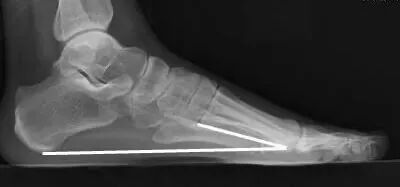

内侧纵弓

• 正常值:113°~130°;

• 测量方法:从跟骨的最低点到距骨头的最低点作一条直线,再从距骨头的最低点到第1跖骨头最低点作一条直线,然后测量两条直线所构成的夹角;

• 扁平足时内弓角增大,弓形足时相反。